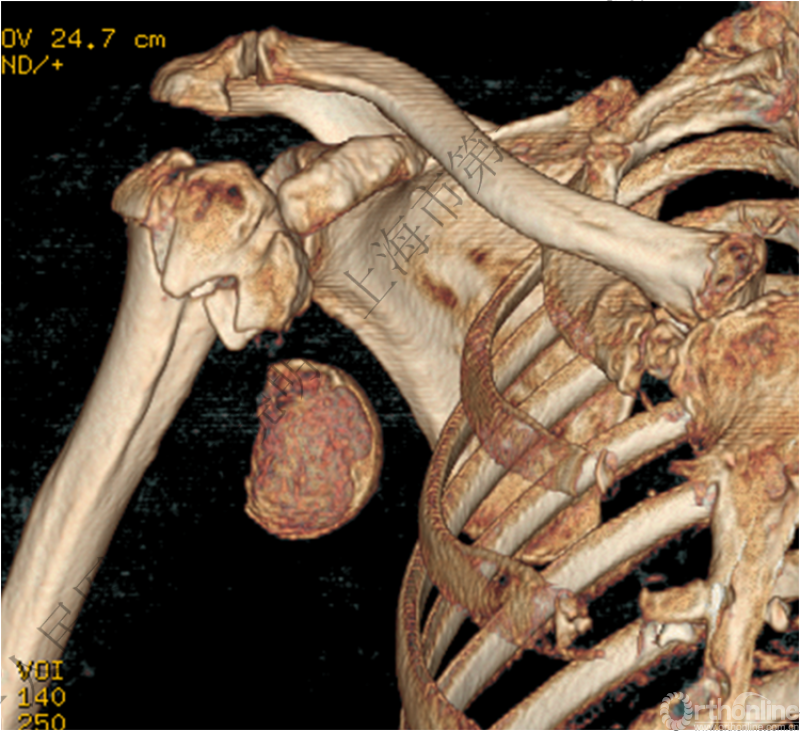

下图考虑为孤立性的大结节骨折?

看完片子,你会发现高质量的平片甚至3D CT也难以发现

X线看不清骨折线,三维CT也看不清

骨折线可以延伸到肱骨头